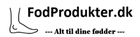

Fra

209,00 kr